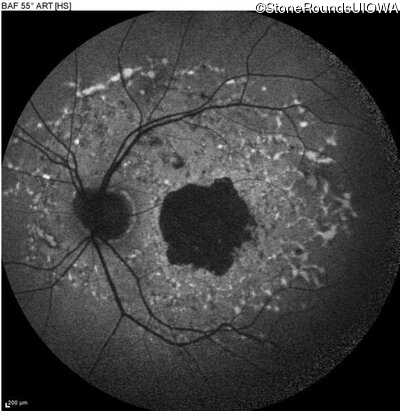

Blue Autofluorescence - Right - 20/125

Exemplar